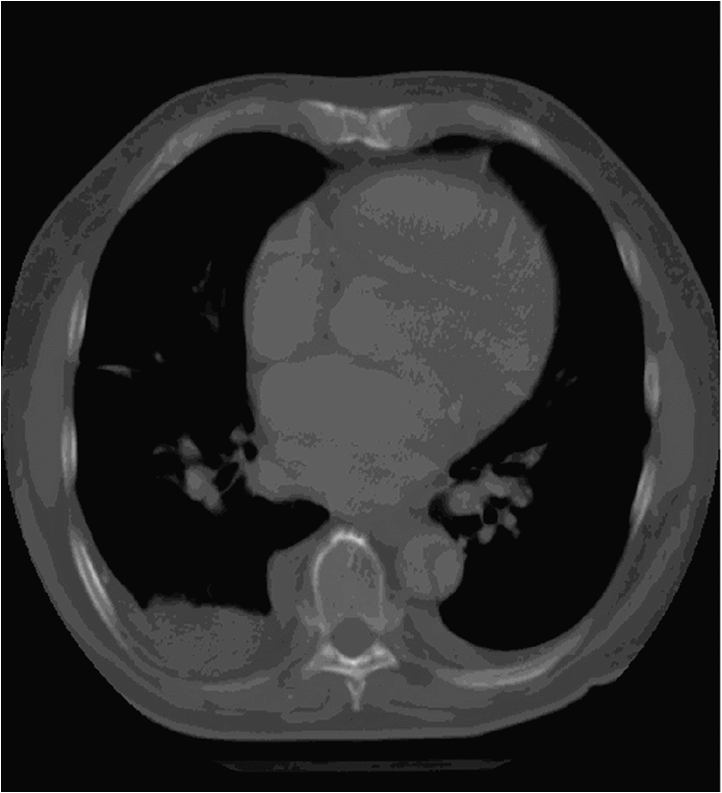

The brightness of the picture can also be altered, making too dark or too light parts of the picture assessable. The windowing allows changing of the brightness and contrast at the same time. If we change them accordingly tissues with different absorption can be highlighted. For example, low brightness and low contrast settings allows good visualization of the bone structures, but other tissues appear moderately pale. High brightness and contrast settings results in a good visualization of the lung tissue while other tissues appear bright and pale.

Figure 3.: The same CT image with soft tissue window (a) and lung window (b)